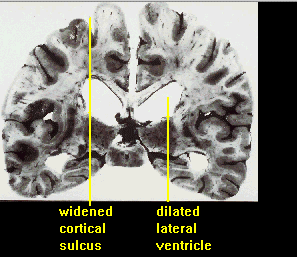

Atrophies (Kurz 1995)

Augmentation du volume des ventricules (et atrophies) (Kurz 1995)